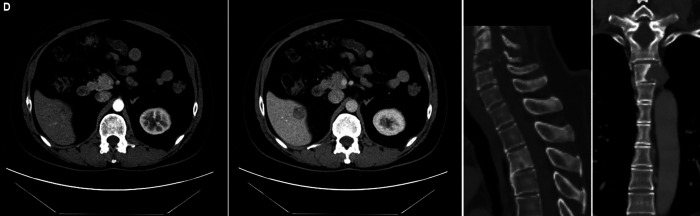

贝伐单抗和阿特唑单抗联合治疗是治疗晚期肝细胞癌(HCC)的首选组合之一,然而单药治疗的证据并不令人信服。我们报告了一个50多岁的男性HCC合并脊柱转移的病例,他对联合治疗有很好的反应。然而,他继发于贝伐单抗后出现了严重的蛋白尿和高血压,在18个周期后不得不停药。在做出明智的决定后,继续使用阿特唑单抗,患者表现出持续的反应。迄今为止,他在停用贝伐单抗后又接受了16个额外周期的atezolizumab单药治疗,并继续显示出持续的反应,目前无进展生存期超过30个月。如我们的报告所述,atezolizumab作为长期单药治疗的有效性是初始联合治疗的残余效应,还是HCC对单独免疫治疗具有内在反应,需要进行前瞻性评估。如何引用本文:Naviwala MSS, Shoaib D, Khan WA等。晚期肝细胞癌停止使用VEGF抑制剂后免疫治疗完全缓解:1例报告。中华肝病与胃肠病杂志;2009;14(2):246-250。

Bevacizumab and atezolizumab combination is one of the preferred combinations for managing advanced hepatocellular carcinoma (HCC), while the evidence on monotherapy with either agent is not convincing. We present a case of a man in his 50s diagnosed with HCC with spinal metastases who showed a good response to combination therapy. However, he developed severe proteinuria and hypertension secondary to bevacizumab, which had to be discontinued after 18 cycles. After an informed decision, atezolizumab was continued and the patient showed a sustained response. Till date, he has received 16 additional cycles of atezolizumab monotherapy after discontinuation of bevacizumab and continues to show a persistent response, with a progression-free survival of over 30 months now. It needs to be prospectively evaluated if atezolizumab's effectiveness as monotherapy for extended periods, as in our report, is a residual effect of initial combination therapy or if HCC is intrinsically responsive to immunotherapy alone.